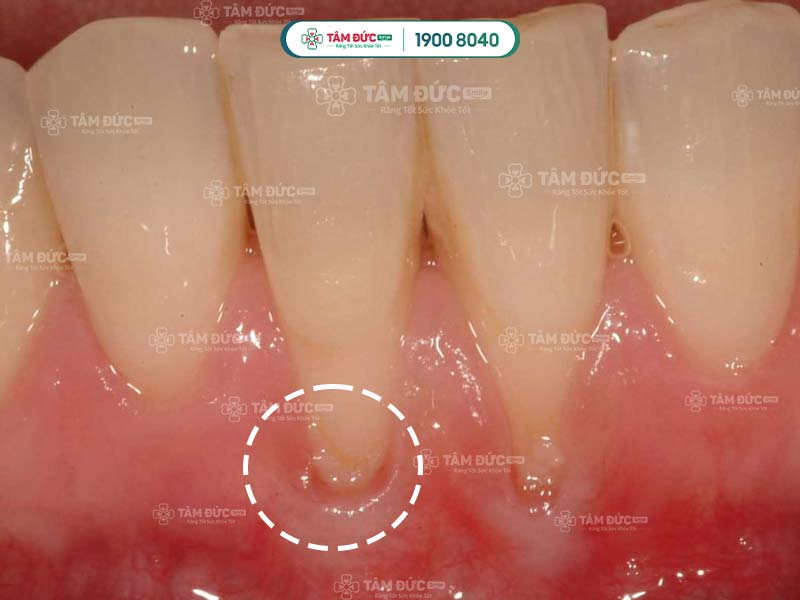

Hiện tượng tụt lợi khá phổ biến, có thể xuất hiện ở cả trẻ em và người lớn. Nếu chỉ quan sát bằng mắt thường, Quý khách sẽ rất khó để phát hiện ra tình trạng này. Đến khi xuất hiện biểu hiện rõ rệt, tụt lợi đã tiến triển sang giai đoạn nghiêm trọng. Lợi bị tổn thương không thể tự chữa lành mà cần được điều trị chuyên sâu tại nha khoa.

Nếu Quý khách bị tụt lợi ở mức độ nghiêm trọng sẽ không thể tự khắc phục tại nhà mà cần đến nha khoa để điều trị. Sau khi thăm khám, bác sĩ sẽ kê đơn thuốc cho Quý khách và tư vấn phương pháp điều trị thích hợp. Đến với nha khoa uy tín, Quý khách có thể ngăn chặn được các biến chứng nguy hiểm do tụt lợi gây ra.

Căn cứ vào mức độ bị tụt lợi và tổn thương, bác sĩ có thể chỉ định điều trị bằng 1 trong 3 phương pháp sau: Lấy cao răng, ghép lợi bằng phẫu thuật hoặc ghép xương răng.